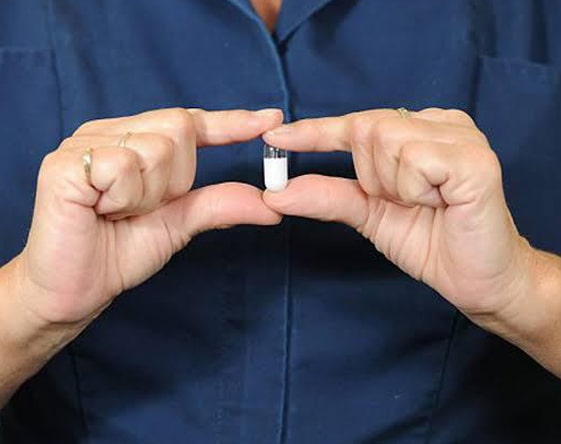

Capsule Endoscopy

Video endoscopy of the bowel. This is a minimally invasive diagnostic procedure that utilizes a...

Read More

Our dedicated team of doctors, healthcare consultants and the trained medical staff impart medical services in the most effective and efficient manner. Apart from the trained staff and healthcare professionals, our infrastructure facilities include modern operation theatre, Cardiac Cath Lab, Intensive Care Unit (ICU) and Liver ICU. The hospital also offers advanced diagnosis facilities so that precise and accurate treatment can be given to patients. This includes Video Endoscopy System, Pediatric, Capsule Endoscopy system, and 24 hrs. Advanced automated and computerized Path Lab.